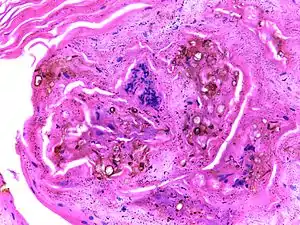

| Micrograph of chromoblastomycosis showing sclerotic bodies | |

The most informative test is to scrape the lesion and add potassium hydroxide (KOH), then examine under a microscope. (KOH scrapings are commonly used to examine fungal infections.) The pathognomonic finding is observing medlar bodies (also called muriform bodies or sclerotic cells). Scrapings from the lesion can also be cultured to identify the organism involved. Blood tests and imaging studies are not commonly used. On histology, chromoblastomycosis manifests as pigmented yeasts resembling "copper pennies". Special stains, such as periodic acid schiff and Gömöri methenamine silver, can be used to demonstrate the fungal organisms if needed.